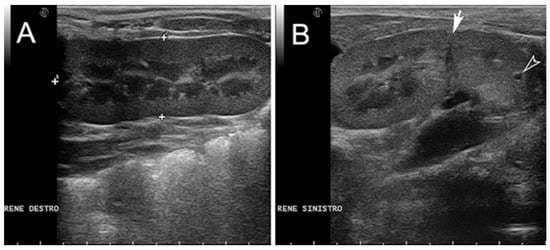

| 1 * | None | partial aplasia of L4, quite complete aplasia of the vertebral canal of L5, partial aplasia with absence of the vertebral canal of L6; scoliotic deviation toward the right. | partial aplasia of S1 with absence of the vertebral canal. | Coccygeal vertebrae: no visible abnormalities other abnormalities: duplication of the first tract of the ureters; caudal dislocation of the left kidney with a dorso-medial bended shape and some cortical small cists |

| 1 * | M | Renal anomalies characterized by a distinct transverse ridge on the lateral surface of the left kidney running backwards. The left kidney is dislocated in caudal abdomen Agenesis of the left adrenal gland | Outer necropsy: there are multifocal areas of ulceration over the hind limb region; these areas show an ovoid morphology, distinct edges and a diameter range from 2 × 2 cm to 5 × 3 cm; There is atrophy of the hind limb muscles and hypertrophy of the forelimbs Inner Necropsy: there is a severe and bi-lateral bronco-pneumonia associated with pulmonary oedema; the mediastinal lymph nodes are slightly enlarged; mild congestion is observed on both natural and cut surface |

| 2 * | M | Renal anomalies characterized by hypoplasy of left kidney associated with dislocation of the left kidney in the caudal abdomen | Outer necropsy There is a focal sub-cutis oedema over the intermandibular region; this area shows an ovoid morphology with indistinct edges Inner Necropsy: there is a moderate bronco-pneumonia associated with severe pulmonary oedema; the mediastinic lymph nodes are slightly enlarged; moderate congestion is observed on both natural and cut surface |

| 3 * | F | Renal anomalies characterized by hypoplasia of left kidney | Inner necropsy: There is a moderate haemorrhagic gastro-enteritis and sero-hemorrhagic effusion in the pericardial sac. Both liver and spleen are congested with slightly enlarged and rounded edges |

| 4 ** | F | Pulmonary atelectasis Renal anomalies characterized by hypoplasia of left kidney associated with dislocation of the left kidney in the caudal abdomen | no macroscopic alteration |

| 7 ** | F | Pulmonary atelectasis Renal anomalies characterized by hypoplasia of left kidney | no macroscopic alteration |